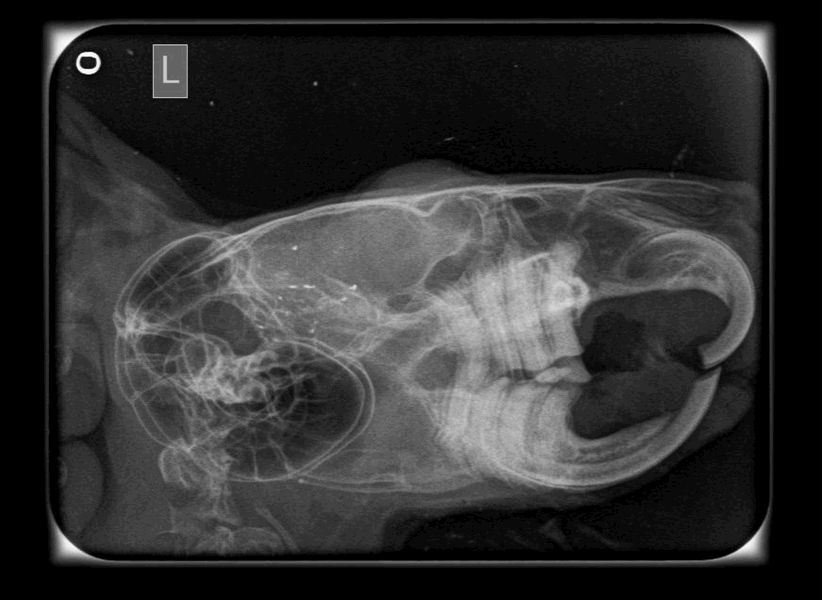

При первичном осмотре ветеринарный врач проводит обследование внутренней полости рта, чтобы оценить состояние зубов. Определить малокклюзию (неправильное смыкание зубов) для опытного врача не составит большого труда, но более сложно установить причину. Далее проводится обследование зубов радиографическим методом (делается снимок головы). Этот метод имеет фундаментальную важность в плане объема информации, которую он легко позволяет получить: форма и структура зубов и корней, структура челюстей, наличие инфекций в области зубов. Сохраненный снимок состояния зубов будет очень полезным для наблюдения за развитием болезни, когда в будущем будут делаться новые снимки. Исходя из осмотра и рентгенологического обследования ветеринарным врачом, совместно с владельцем, выбирается тактика дальнейшего лечения и восстановления питомца.